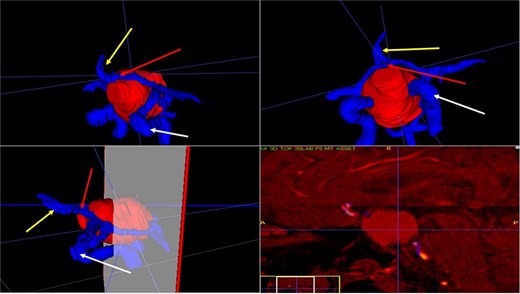

A 68-year-old male patient with an 8-year history of gradual loss of visual acuity. An MRI study was performed with the following sequences: T1, T2, and T1 with contrast. When performing the three-dimensional segmentation, we realized the intimate relationship that the dorsum of the tumor had with the basilar artery; its dolichoectatic course on the dorsal surface of the tumor was what we paid the most attention to and what made us plan a better transnasal approach and avoid the traction of the capsule mainly the dorsal region (Fig. 6).

(A, B and C) MRI of pituitary marcoadenoma in coronal, axial and sagittal sections, contrasted T1, T2, and T1 sequences. (D and E) Planimetric segmentation with 3D reconstruction of the basilar and carotid system. White arrow, relationship of the dorsum of the tumor with the basilar artery.

A 42-year-old male patient presented with a history of difficulty seeing in both temporal fields. The examination confirmed said bitemporal hemianopsia. We observed a sellar lesion in the MRI (T1, T2, and T1 sequences with contrast). With the segmentation, we were able to almost reconstruct the cavernous sinus and the internal carotid artery wholly in its intracavernous and clinoid portion and thus take more caution in the most rostral and dorsal region of the tumor since it was the site where both clinoid carotid arteries were closest each other (Fig. 7).

MRI and 3D volumetric segmentation of pituitary macroadenoma. Note the proximity of the internal carotid artery (green) in the most rostral and dorsal region of the tumor (red). Cavernous sinus (blue).